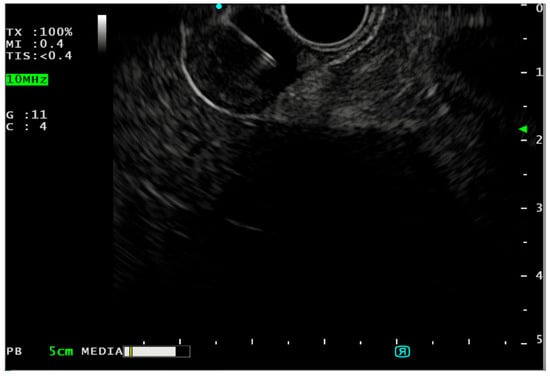

4. Endoscopic Ultrasound (EUS)

- Pallio, S.; Crinò, S.F.; Maida, M.; Sinagra, E.; Tripodi, V.F.; Facciorusso, A.; Ofosu, A.; Conti Bellocchi, M.C.; Shahini, E.; Melita, G. Endoscopic Ultrasound Advanced Techniques for Diagnosis of Gastrointestinal Stromal Tumours. Cancers 2023, 15, 1285. [Google Scholar] [CrossRef]